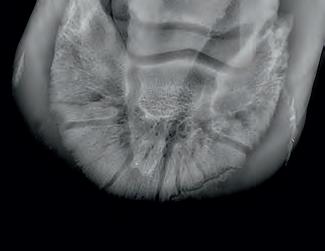

Radiographic proof in clinical results

BONE Gold nutritional bone joint and collagen supplement was formulated to provide some of the essential amino acid requirements of collagen type I, II and III (found in bone and connective tissue) in addition to supporting the nitric oxide pathway which has been found to assist in the formation of bone callus postinjury.

Veterinary surgeons have recommended that Bone Gold may assist with sore shins, tendon injuries, ligament injuries, osteoarthritis and post-surgery in horses and polyarthritis, geriatric osteoarthritis, and post-surgery in dogs.

Here is a veterinary radiographic report on a horse with a fracture evident on the medial toe and after treatment and feeding Bone Gold during this period. More information on these products can be found at www.vetgold.com.au

VETERINARY RADIOGRAPHIC REPORT

HORSE: "XXXXXXXX"

DATES OF EXAMINATION: 26TH AUG, 21ST OCT 21 & 17TH NOV '21

PLACE: XXXXXXXXXX FARM

XXXXXXX's left and right front feet were radiographed on 26th Aug, 21st Oct (8 weeks) and again on the 17th Nov '21(12 weeks).

RADIOGRAPHS:

26.08.21: Right Front: Large P3 solar margin fracture evident on medial toe 32.6mm x 4.1mm with approximately 1.4mm separation from parent bone as below left image.

21.10.21: Right Front: Fine residual 4.2mm fracture still evident, approximately 90% resolution

17.11.21: Right Front: Fracture fully resolved

RECOMMENDATIONS:

Radiographic results as of the 17th Nov '21 show total resolution of the original fracture.

XXXXXXX was reshod today utilising off an alloy shoe with a toe clip - inner circumference seated out to avoid any sole pressure.

The horse can return to training. Please do not hesitate to contact me if you have any further queries

COMMENTS:

Solar margin Type IV fractures of this magnitude have well-documented internationally published healing rates of 7 - 12 months. Full resolution of these fractures is rare as most often the fracture fragments are resorbed.

Full resolution in a 3 month period was not anticipated.

The horse was on Bone Gold 3 x scoops fed once per day for this period.

"Go to our webpage or scan the QR Code to see more Bone Gold Radiographic results"